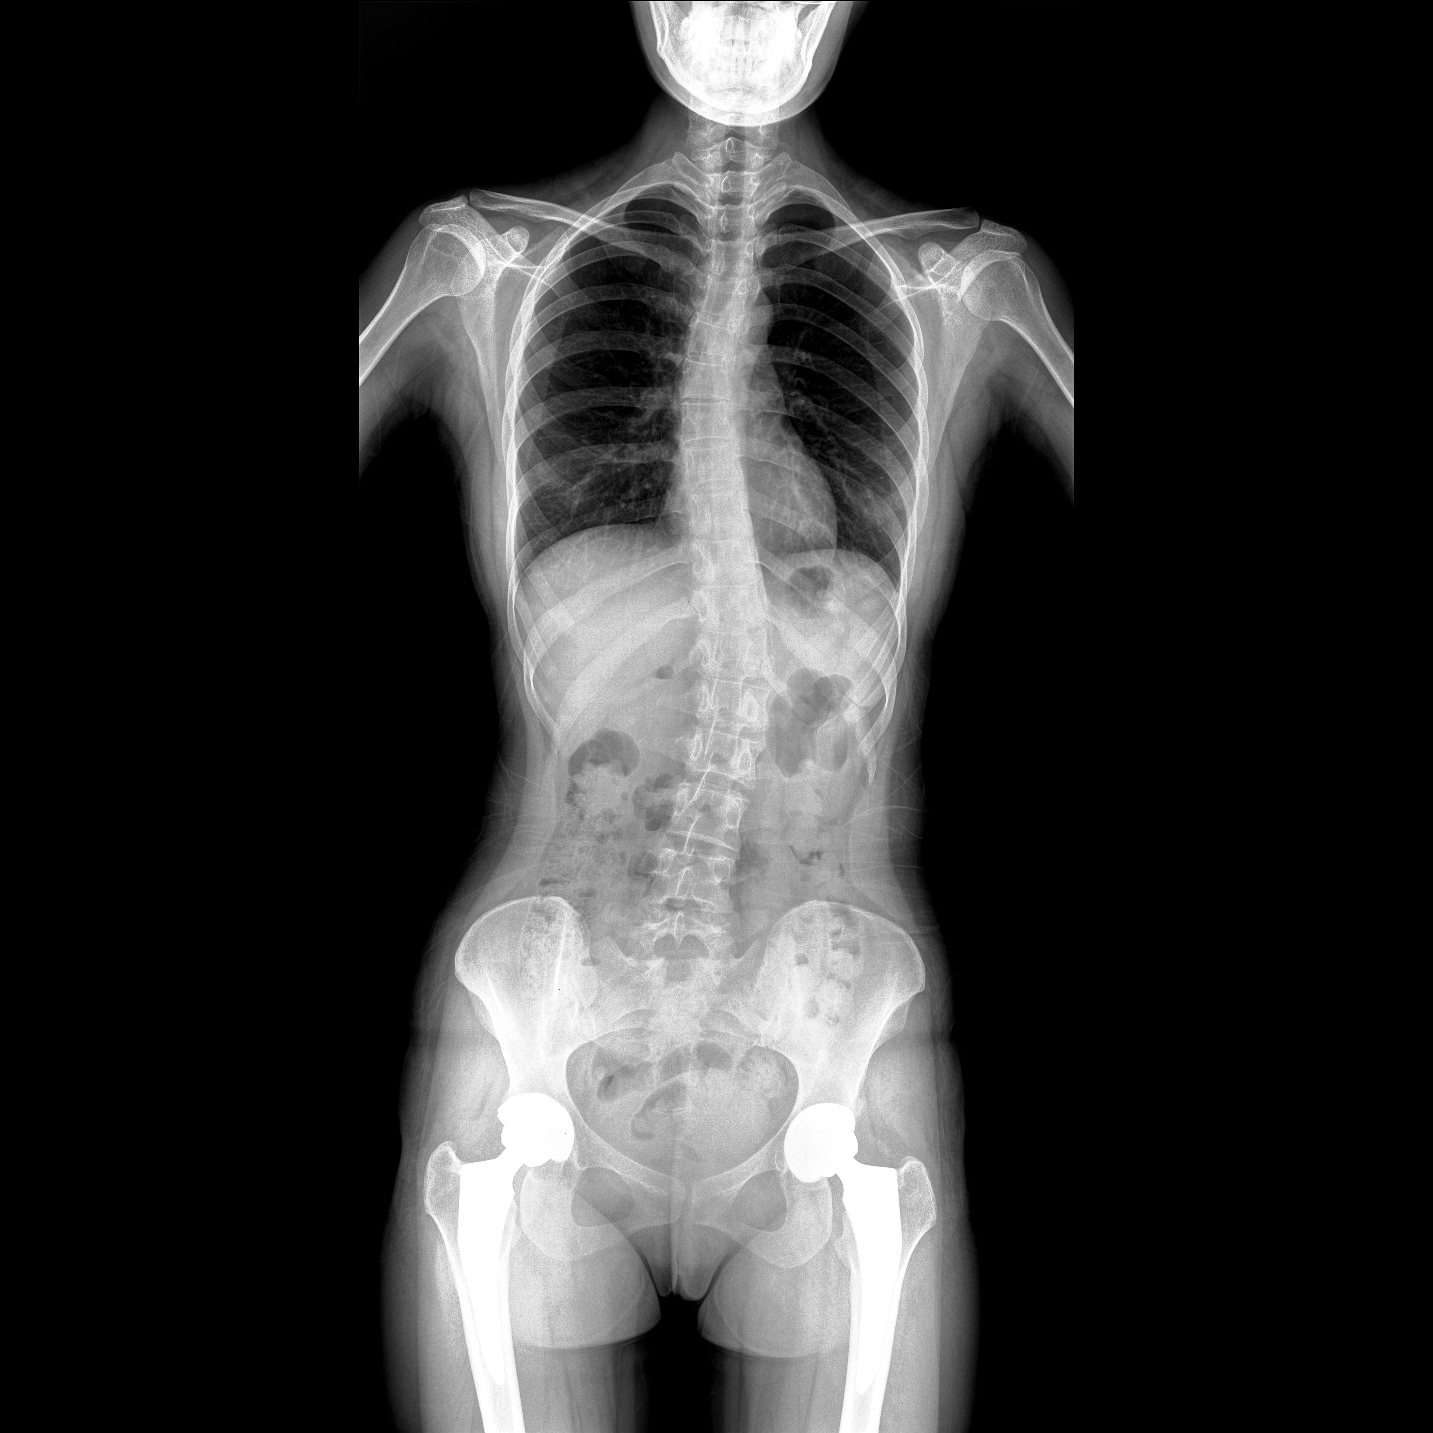

支持全脊柱攝影、雙下肢攝影、脊髓造影、復雜創(chuàng)傷、人工關節(jié)置換、關節(jié)損傷的修復重建等大視野臨床應用

17"*34"有效視野,一次成像不拼接。相較于多張攝影再軟件拼接的DR設備,PLX8600解決了拼接圖像存在密度不均勻,拼接處圖像配準和放大效應等問題,給臨床帶來了大視野影像解決方案,可一次性覆蓋全脊柱或雙下肢影像。